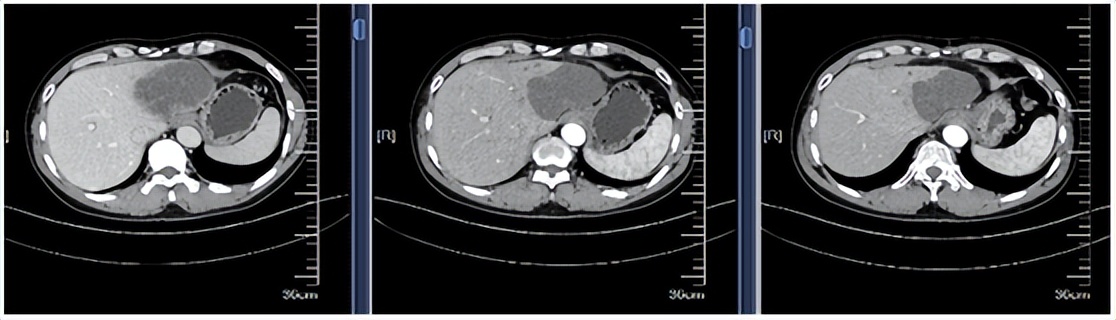

57岁的王先生(化名)因上腹部不适就诊,影像学检查:胸部+全腹部CT平扫+三期增强提示肝左叶占位(范围约8.5cm*6.0cm)伴肝内多发低密度灶(见下图)。

王先生行第一、二周期化疗联合免疫治疗后,再序贯放疗,1个月后复查肿瘤标志物CA199明显下降,胸部+腹部CT平扫+增强提示病灶较前缩小。患者行第三、四周期化疗联合免疫治疗后,复查CA199降至正常范围,胸部+腹部CT平扫+增强提示病灶较前缩小。

患者影像学复查结果